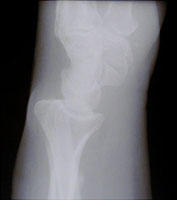

- Click on the image for a larger versionAPA radiograph of the wrist. There is irregularity of the distal radial margin. In addition, a fracture of the distal radius is appreciated.

The Barton fracture consists of an intraarticular fracture of the dorsal margin of the distal radius. The fracture line is oblique and extends to the radiocarpal joint. The fracture results from a fall on an outstretched hand.